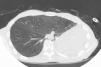

Tras 15 meses de evolución favorable, el paciente comenzó a presentar disnea progresiva y a mínimos esfuerzos, asociada a estridor inspiratorio y ocasionales dolores pleuríticos izquierdos. La tomografía computarizada de tórax (fig. 1) mostró los cambios posquirúrgicos de la neumonectomía izquierda: desplazamiento mediastínico, ausencia de líquido en la cavidad posneumonectomía, hiperinsuflación del pulmón derecho y compresión extrínseca del bronquio intermediario entre la cara anterolateral del cuerpo vertebral y la arteria pulmonar derecha. La luz bronquial era de aproximadamente 3mm en una extensión de 2cm al nivel del bronquio intermediario. Estos hallazgos quedaron confirmados en la fibrobroncoscopia, que descartó signos de broncomalacia o lesiones endoluminares.

Síndrome posneumonectomía izquierda: tomografía computarizada de tórax efectuada a los 15 meses de una neumonectomía izquierda, en la que se observan la ausencia de la cavidad pleural posneumonectomía, con marcado desplazamiento mediastínico; aumento del volumen pulmonar derecho, que traspasa la línea media, y estenosis por compresión del bronquio intermediario entre el cuerpo vertebral y la arteria pulmonar derecha (flecha).